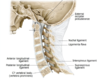

__-__ joints consist of an articulation between the spine and the cranium. They permit motion in multiple planes stabilized by anterior and posterior atlanto-occipital membranes.

atlanto-occipital joints consist of an articulation between the spine and the cranium. They permit motion in multiple planes stabilized by anterior and posterior atlanto-occipital membranes.

The atlanto-axial joints are stabilized by ligaments:

- __ ligaments of the atlas (with longitudinal fascicles = cruciate ligaments of the atlas)

- • __ ligaments

- __ membrane (posterior longitudinal l.)

- __ ligament (supraspinous l.)

The atlanto-axial joints are stabilized by ligaments:

- transverse ligaments of the atlas (with longitudinal fascicles = cruciate ligaments of the atlas)

- • alar ligaments

- tectorial membrane (posterior longitudinal l.)

- nuchal ligament (supraspinous l.)